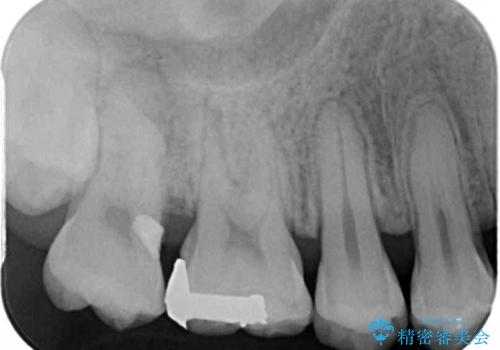

また、奥歯の銀歯をゴールドにしたいとのことで、並行してPGAインレーにて修復治療を行うこととしました。